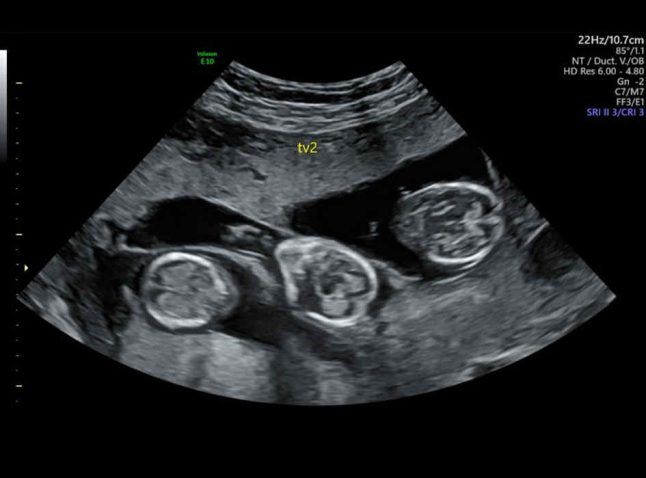

Ultrazvok. Foto: Profimedia

Zgodba je dokaz, da se tudi iz majhnega upanja lahko rodi čudež. To dobro ve tudi Švedinja Marie Gustavsson (50), ki je kljub napovedim zdravnikov osem mesecev po postopku umetne oploditve rodila trojčke, sina Charlieja ter hčerki Lorinne in Laro.

“Pri 50 letih sem rodila trojčke, potem ko so mi rekli, da so naše možnosti le 5-odstotne,” pravi ženska, ki je nekoč delala kot medicinska sestra. Marie in njen mož sta že imela štiri skupne sinove, ko sta se odločila, da bi imela še enega otroka. Čeprav so jima zdravniki priporočali zmanjšanje števila zarodkov, je Marie to zavrnila.

“V prejšnjih nosečnostih nisem imela nobenih težav in vsakič sem hitro zanosila. Kljub temu zaradi svoje starosti nisva mislila, da bo tokrat uspelo v prvem poskusu. Zato smo prenesli tri zarodke, da bi povečali možnosti. Zdravniki so rekli, da obstaja le 5-odstotna možnost, da se bodo ugnezdili, a na koncu so se vsi trije. Bila sem šokirana in presrečna. To je bilo fantastično darilo,” pripoveduje Švedinja.